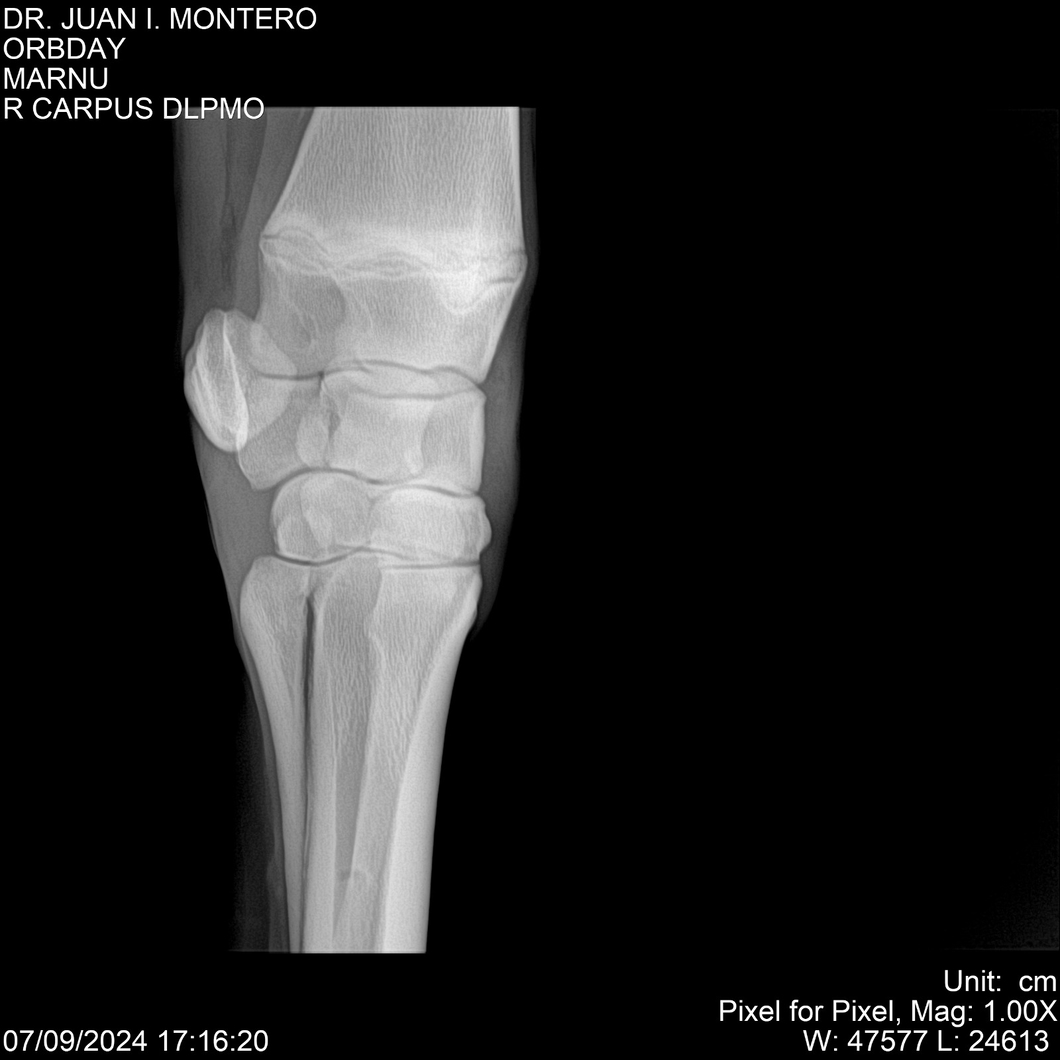

• Empresa: Abelenda N. R., Walter Hugo